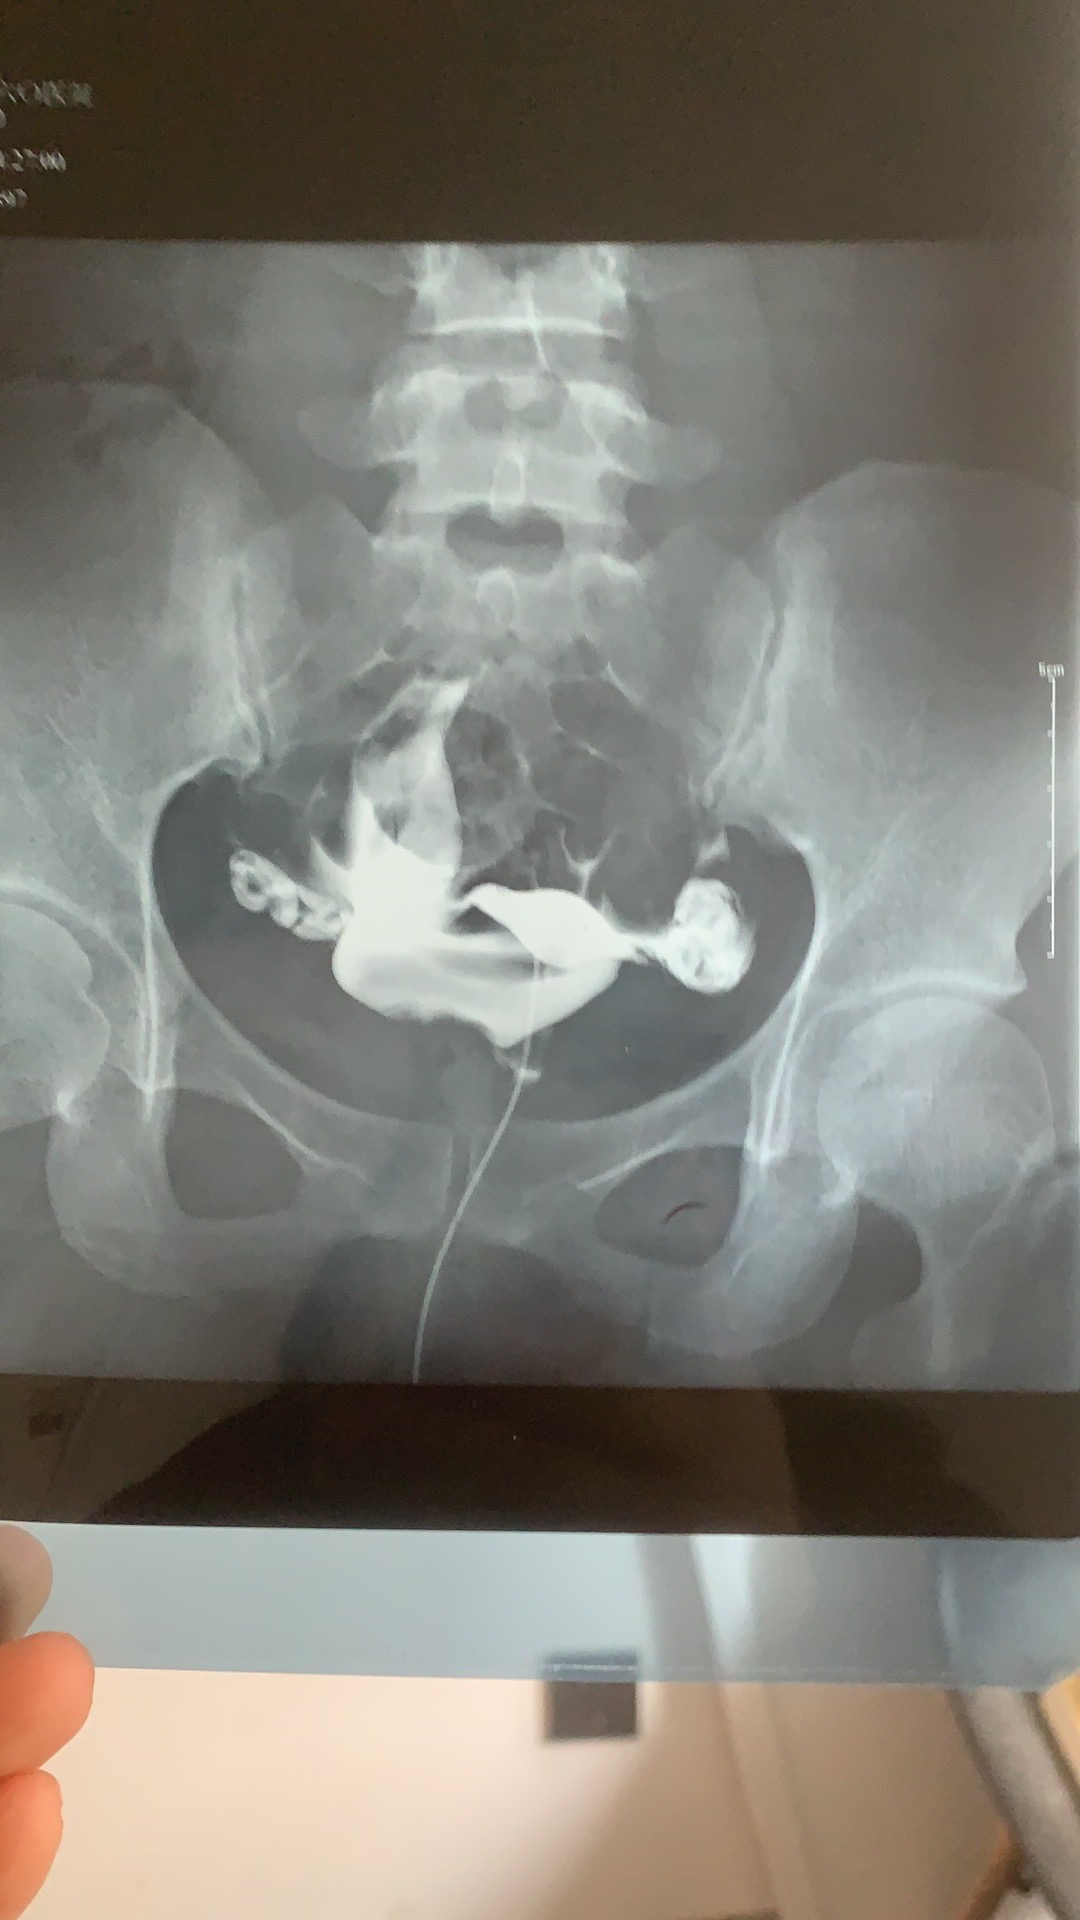

你好,这个输卵管两侧考虑均有输卵管积水,输卵管积水会沿着输卵管进入宫腔,如果遇胚胎,有可能会将胚胎冲出宫腔,引起流产或种植失败,建议你先做腹腔镜,把输卵管积水处理后再做试管

一侧输卵管积水比较严重,建议先处理后再进行移植,积水倒流有可能影响胚胎着床

如果是输卵管积水,建议结扎输卵管或者切除后再移植。否则,积水倒流,会影响胚胎着床。

输卵管积水逆流入宫腔导致胚胎着床失败,建议先处理积水再移植。做宫腹腔镜联合手术根据术中情况决定是清除积水还是行输卵管结扎术。